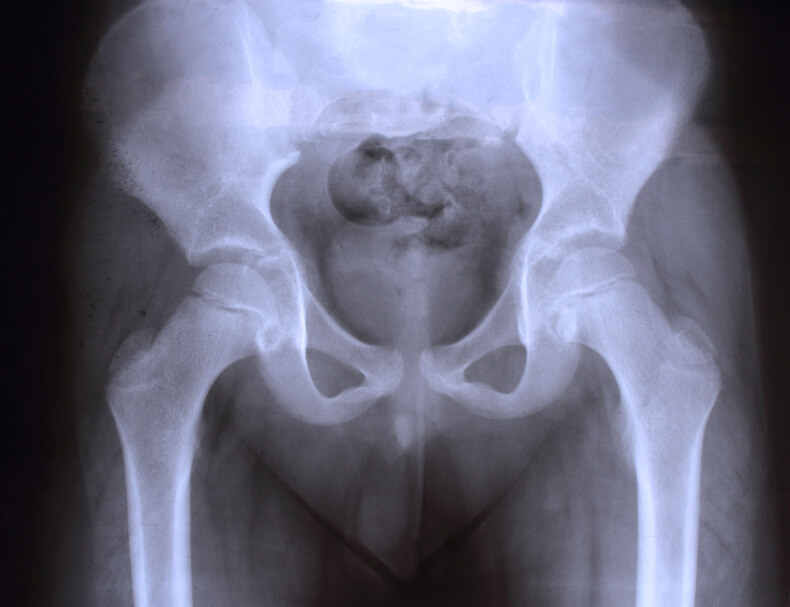

Bei geringen Unterschieden hat das Kind keine Symptome. Ist die Beinlängendifferenz genug ausgeprägt, kann es aber z. B. zu einem Hinken, einer Seitverbiegung der Wirbelsäule (Skoliose) oder zu einer eingeschränkten Beweglichkeit eines Hüft-, Knie- oder Sprunggelenkes kommen. Ob die Beinlängendifferenz Ursache oder Folge dieser Symptome ist, muss dann vom Kinderorthopäden geklärt werden.

Kleinere Unterschiede sind nicht behandlungsbedürftig, da die meisten Menschen geringe asymptomatische Beinlängendifferenzen aufzeigen. Beinlängendifferenzen bei Kindern müssen beobachtet und unter Umständen behandelt werden. Da die Beine die Basis unserer Statik darstellen, kann eine Beinlängendifferenz Veränderungen in der Körperhaltung beziehungsweise in der Wirbelsäule oder am Bewegungsapparat hervorrufen. Der menschliche Körper hat zwar Kompensationsmöglichkeiten, dennoch sind bei zu großen Beinlängendifferenzen langfristig schmerzhafte Veränderungen die Folge. Je nach Ausprägung kommen Einlagen, Schuhzurichtungen bis hin zu Etagenschuhen oder orthopädietechnische Beinorthesen als konservative Therapiemöglichkeiten infrage. Operativ kommen wachstumslenkende Maßnahmen genauso zum Einsatz wie verkürzende oder verlängernde Verfahren.